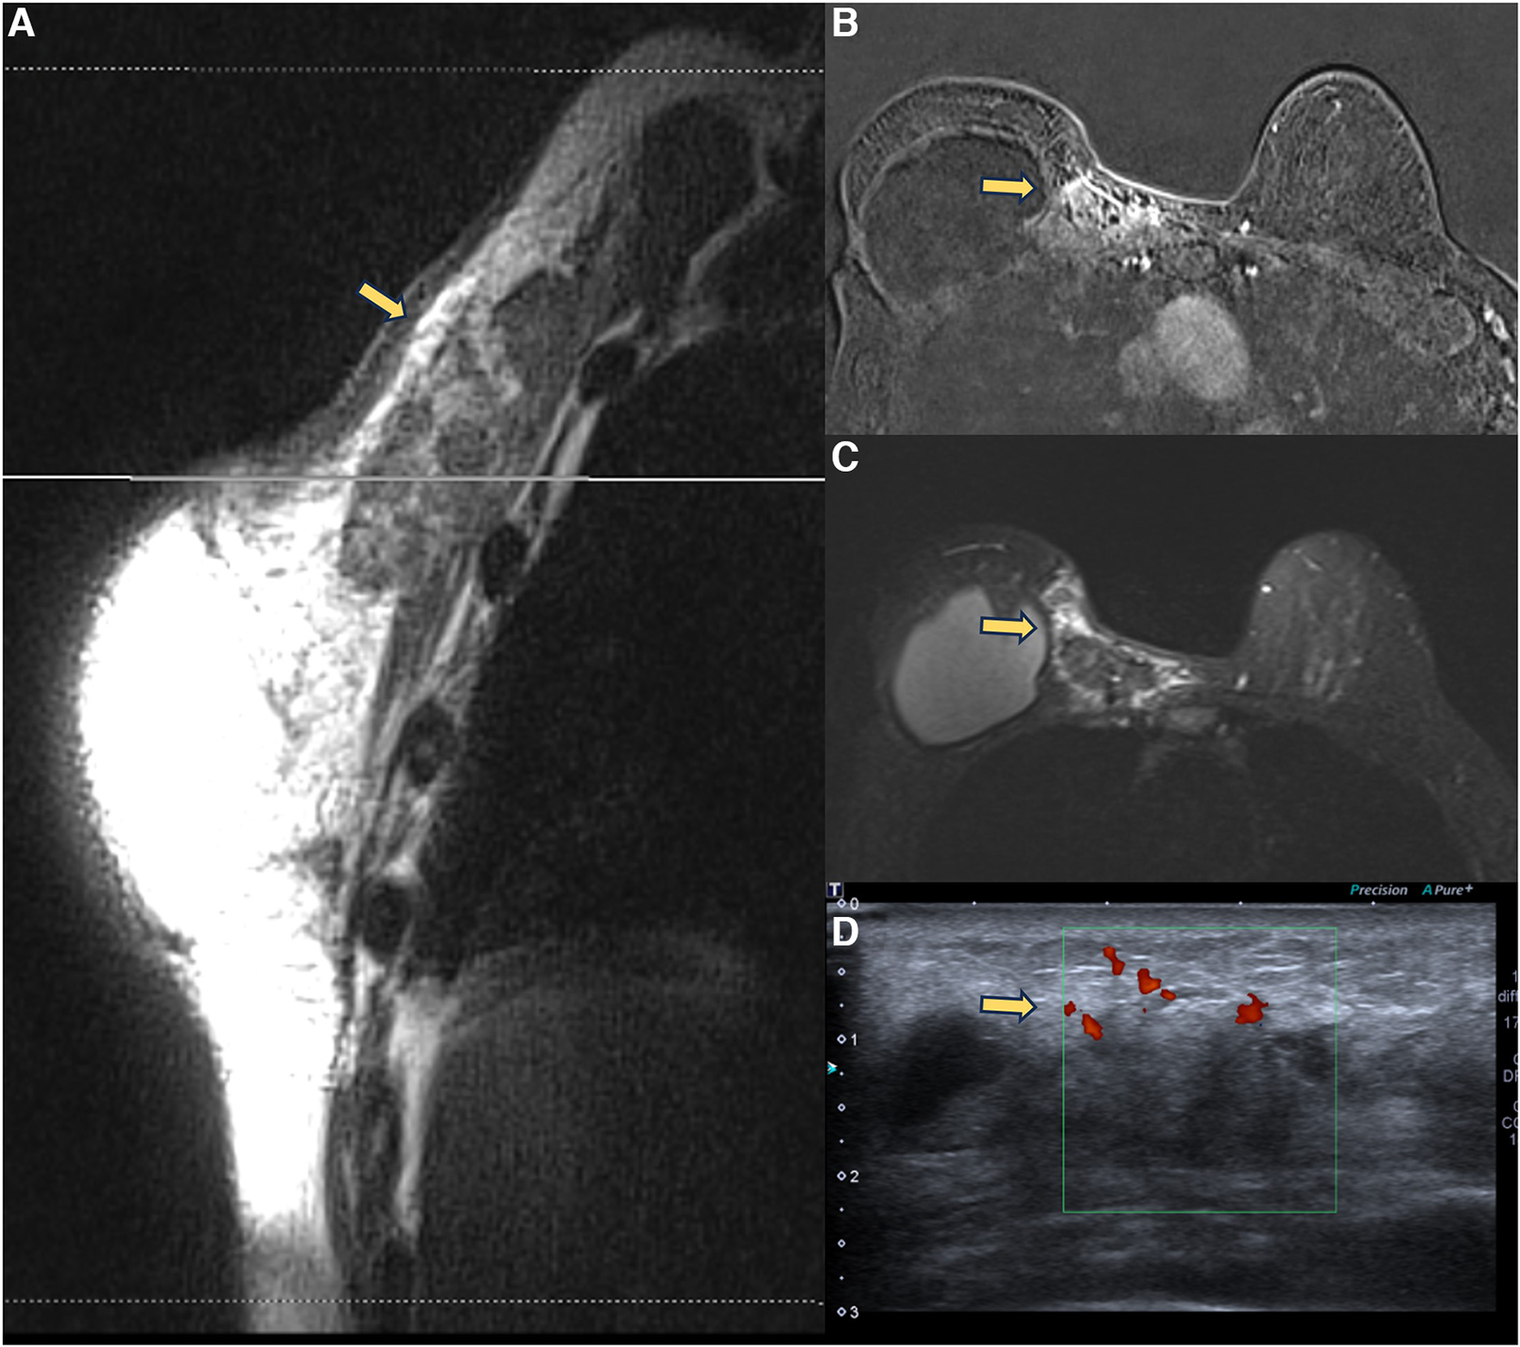

In 2021, we published a magnetic resonance classification proposal for fibrous capsules, divided into four evolutionary categories, with category 4 representing changes indicative of a pericapsular inflammatory process. The classification graduates the degree of fibrous capsule impairment and the association with an acute inflammatory process (33) (Figure 1).

Figure 1. A 58-year-old woman with silicone implants for 6 years, with suspicion of right capsular contracture. The multiplanar intensity projection (MIP) reconstruction (A), the axial post-contrast image (B), and the flow intensity image (C) show capsular contracture with inflammatory signs in the right breast (yellow arrows). The green arrows show non-mass enhancement of the pericapsular tissue, especially in the right breast. The right implant is an example of fibrous capsule grade 4 and the left as a grade 3.